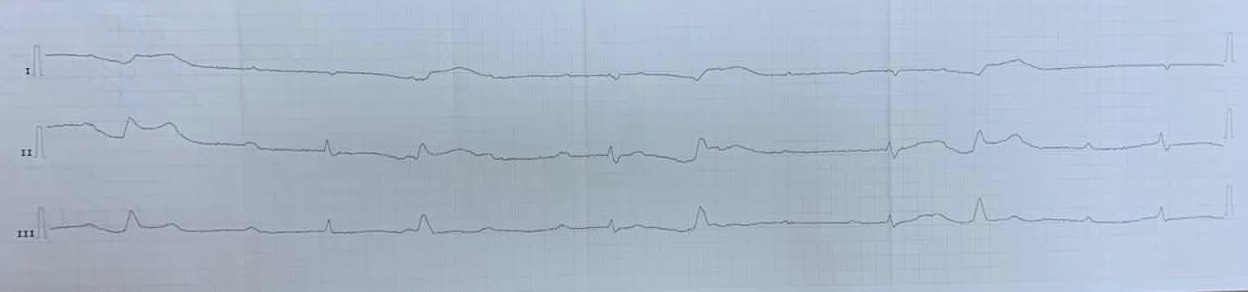

ЖТ

Вложения:

IMG_4388.JPG

IMG_4388.JPG [ 385.05 KiB | Просмотров: 32416 ]